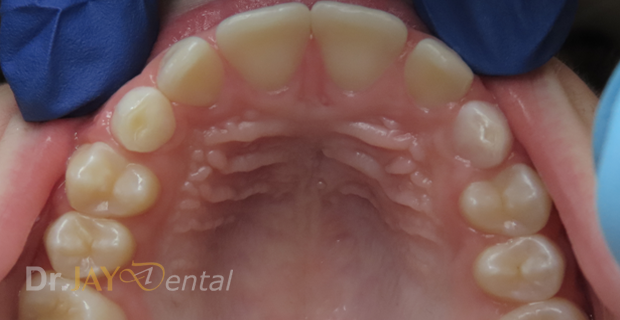

upper arch crowding getting resolved in 4 months using light wire appliances

Before

After